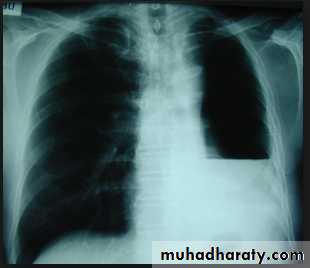

On a posteroanterior chest x-ray (A), the left hemithorax is very dark or lucent because the left lung has collapsed completely (white arrows).The tension pneumothorax can be identified because the mediastinal contents, including the heart, are shifted toward the right, and the left hemidiaphragm is flattened and depressed. A computed tomography scan done on a different patient with a tension pneumothorax (B) shows a completely collapsed right lung (arrows) and shift of the mediastinal contents to the left.

Tension Pneumothorax. Portable chest film in a 43-year-old woman with ARDS shows a large right pneumothorax with mediastinal shift and ipsilateral diaphragmatic depression, suggesting tension.

Air was evacuated under pressure during emergent placement of a right chest tube.